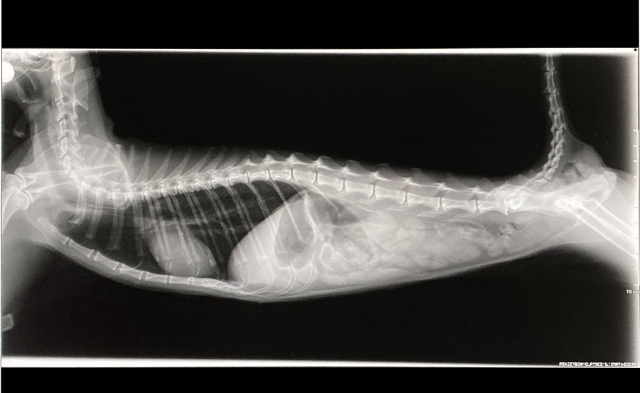

1. 診察と検査

まずは問診、触診、X線検査などで腸内の状態を確認します。必要があれば超音波検査を行い、腫瘍や腸閉塞といった他の疾患の有無もチェックします。